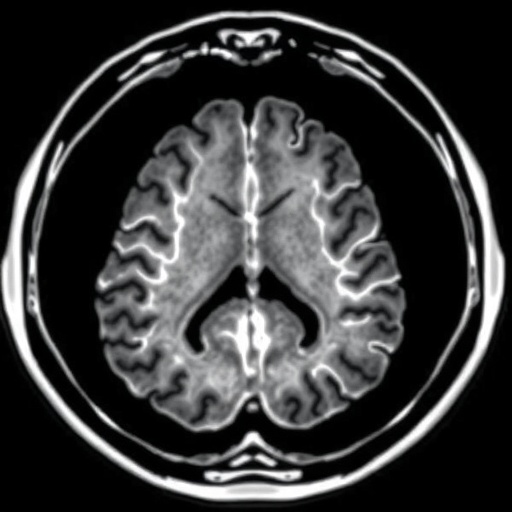

Lung cancer remains one of the deadliest malignancies globally, frequently complicated by the development of brain metastases, which significantly worsen patient outcomes. Traditional imaging methods, particularly craniocerebral magnetic resonance imaging (MRI), are the current standard for detecting BM, offering high sensitivity and detailed anatomical resolution. However, MRI’s ability to characterize metabolic activity or fibroblast activation within lesions is limited, necessitating adjunctive diagnostic tools.

The study prospectively enrolled 18 patients between December 2020 and October 2021, all of whom had histologically confirmed lung cancer and were clinically suspected of harboring brain metastases. Each patient underwent paired imaging with ^18F-FAPI PET/CT and craniocerebral MRI to facilitate a comparative analysis of detection rates. This concurrent imaging strategy enabled precise assessment of ^18F-FAPI PET/CT’s performance relative to the MRI gold standard.